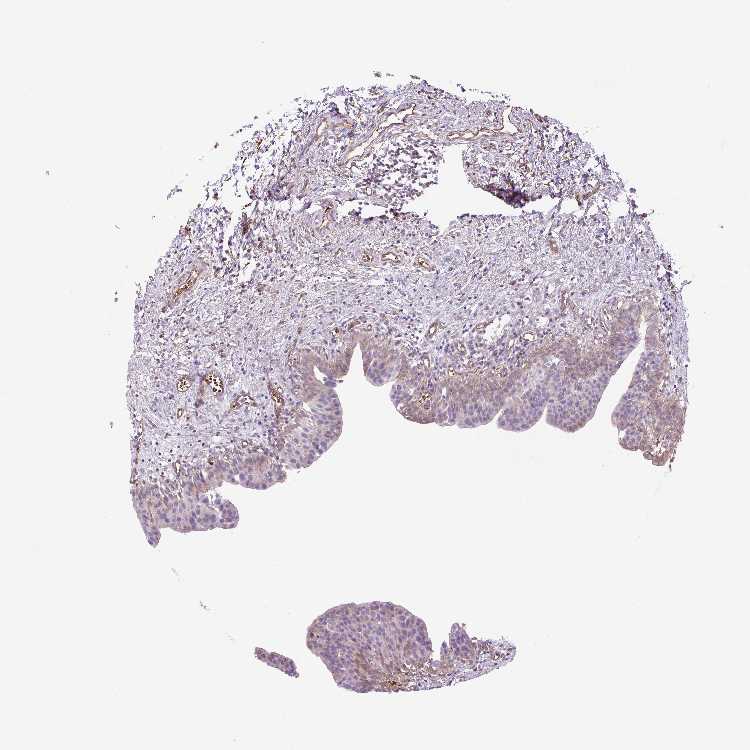

OR13D1